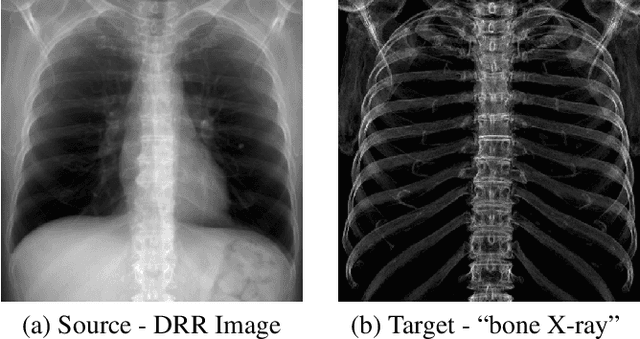

In this paper, we present a deep learning-based image processing technique for extraction of bone structures in chest radiographs using a U-Net FCNN. The U-Net was trained to accomplish the task in a fully supervised setting. To create the training image pairs, we employed simulated X-Ray or Digitally Reconstructed Radiographs (DRR), derived from 664 CT scans belonging to the LIDC-IDRI dataset. Using HU based segmentation of bone structures in the CT domain, a synthetic 2D "Bone x-ray" DRR is produced and used for training the network. For the reconstruction loss, we utilize two loss functions- L1 Loss and perceptual loss. Once the bone structures are extracted, the original image can be enhanced by fusing the original input x-ray and the synthesized "Bone X-ray". We show that our enhancement technique is applicable to real x-ray data, and display our results on the NIH Chest X-Ray-14 dataset.